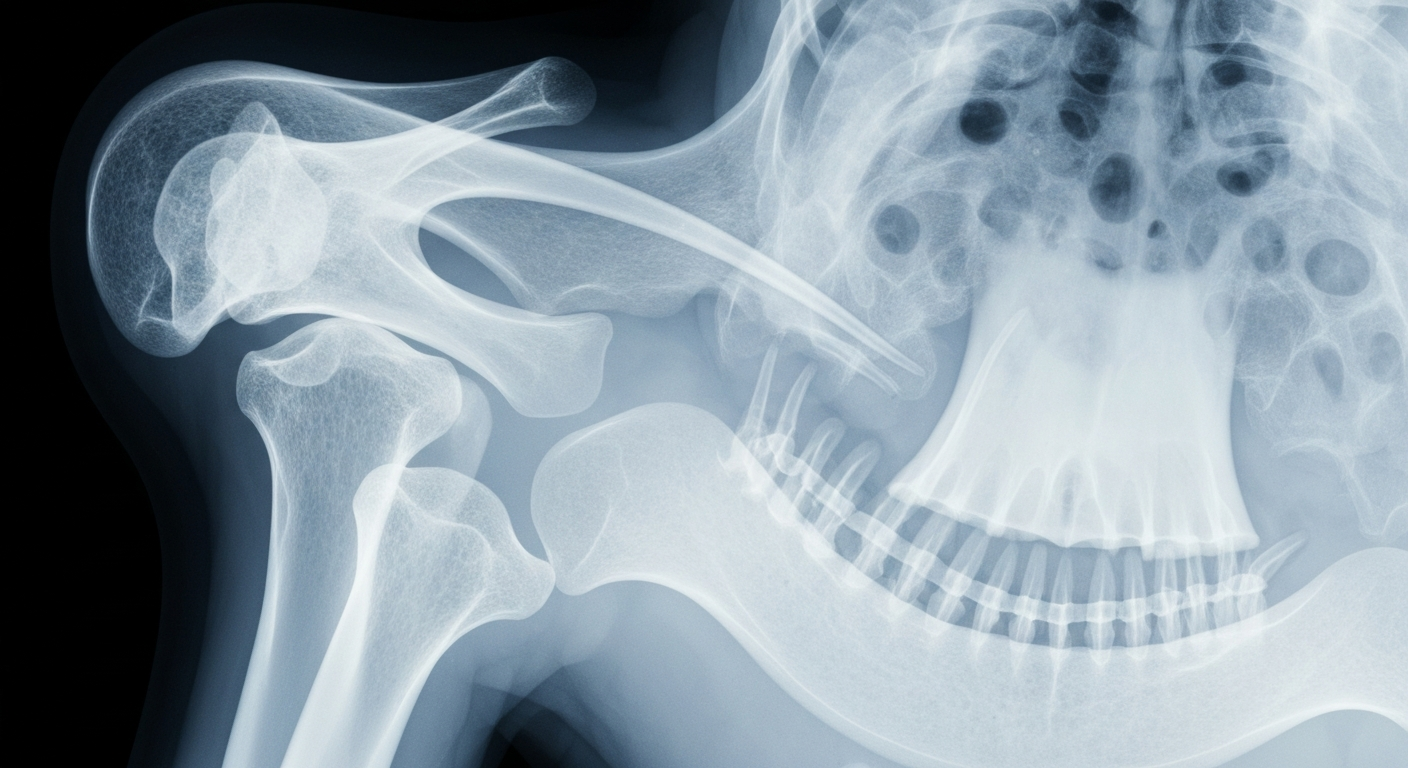

An advanced imaging technique provides a revealing look at the complex anatomy of the oropharynx, potentially aiding in the early detection and risk assessment of HPV-related cancers.Columbus TodayA study published in JAMA Otolaryngology-Head & Neck Surgery found that a blood test for circulating tumor human papillomavirus DNA (ctHPVDNA) may improve risk assessment in patients undergoing surgery for HPV-related oropharyngeal cancer. The researchers assessed clinicopathologic variables associated with ctHPVDNA before and after surgery, and found that higher estimated glomerular filtration rate and higher pathologic N stage were independently associated with higher preoperative ctHPVDNA levels, while perineural invasion and pathologic extranodal extension were associated with lower ctHPVDNA levels.